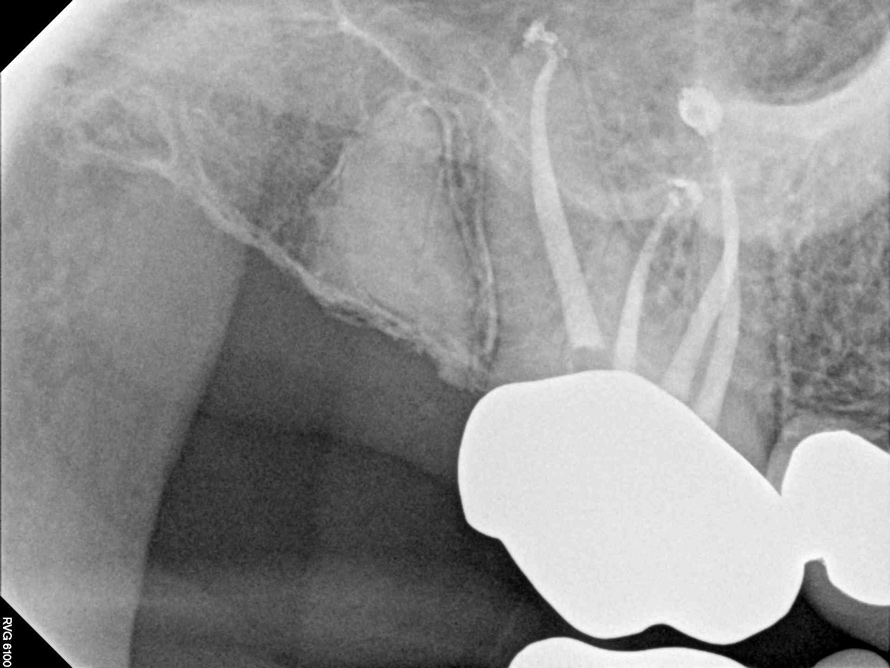

Fig 2. Tooth No. 14 was treated with silver points. In Figure 2, tooth No. 18 with mesial canals treated with Sargenti paste. The hallmark radiographic appearance of this technique is the light radiopacity within the canal system, as in Figure 3.

Fig 3. Tooth No. 14 was treated with silver points. In Figure 2, tooth No. 18 with mesial canals treated with Sargenti paste. The hallmark radiographic appearance of this technique is the light radiopacity within the canal system, as in Figure 3.

No obturation material nor method for placement available today is truly ideal. Though the dental manufacturing industry periodically introduces new materials with promise, many have been abandoned given major deficiencies in their efficacy or safety.  For example, silver points were once well accepted as root filling materials, but were abandoned decades ago due to moisture-related corrosion creating leakage and staining.4 Additionally, silver points proved especially difficult to remove during orthograde retreatment procedures due to the corrosion (Figure 2). Other historic techniques, like the now infamous paraformaldehyde-based Sargenti Method, proved dangerous due to toxicity to the adjacent periapical and surrounding tissues5 (Figure 3). More recently, the technique of complete bioceramic cement obturation has been developed. Though useful with open apices for apexification or in repairing other root deficiencies such as strip perforations, its inability to be removed readily from the root canal system means it should be reserved for those cases lacking suitable alternatives.6